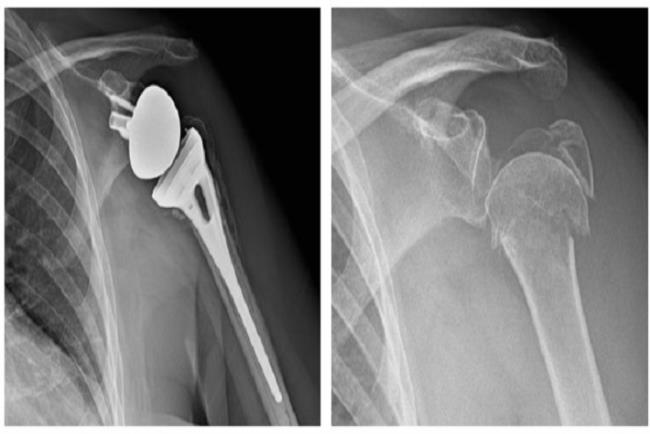

שבר פריקה מורכב בראש עצם הזרוע (בצילום מימין), שטופל בהחלפה חלקית של מפרק הכתף (בצילום משמאל).

שבר מורכב בראש עצם הזרוע (בצילום מימין), שטופל ניתוחית בהחלפת כתף הפוכה (בצילום משמאל).